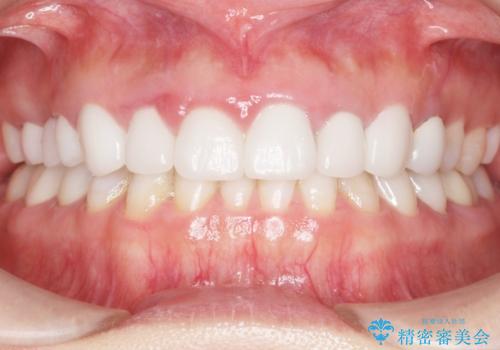

かぶせものと歯ぐきの境目が黒い 40代女性

- 被せ物と歯ぐきの境目が黒いことを気にされ、来院された患者様です。

精査したところ、メタルボンドクラウンの金属部分が露出し黒く見えていました。

患者様のご希望により、金属を使わないオールセラミックのブリッジによる補綴治療を行いました。

自然な仕上がりと咬み心地に喜んで頂けました。